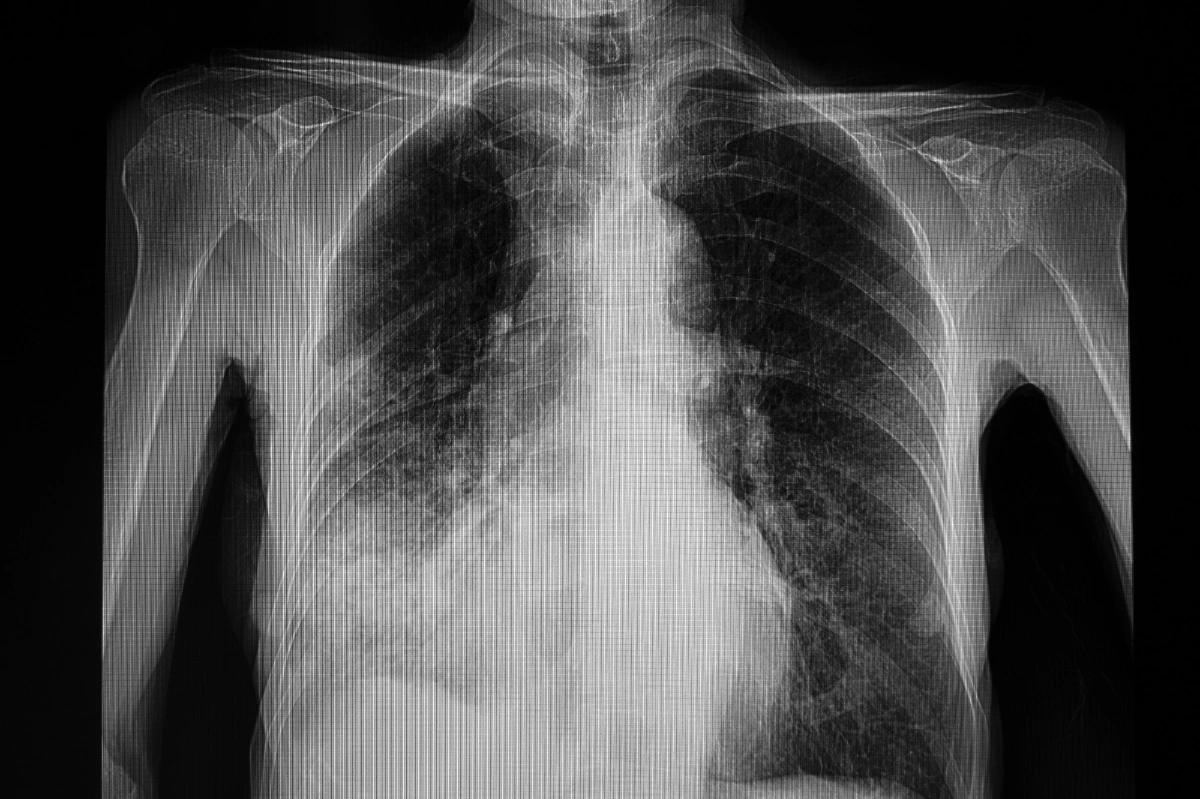

คนที่เสียชีวิตด้วยโรคปอดบวมนั้น สาเหตุส่วนใหญ่มาจากปอดมีการอักเสบรุนแรงและติดเชื้อในกระแสเลือด เนื่องจากได้รับการรักษาช้า รวมถึงยังเป็นผู้ที่อยู่ในกลุ่มเสี่ยงเบื้อนต้นตามที่กล่าวมา แต่แท้จริงแล้วโรคปอดบวมเป็นโรคที่สามารถรักษาให้หายขาดได้หากได้รับการรักษาที่ทันท่วงที หากใครที่มีอาการเข้าข่ายแพทย์จะทำการเอกซเรย์ปอดเพื่อหาความผิดปกติ โดยสังเกตได้จากปอดจะมีฝ้าสีขาวอย่างชัดเจน แต่ในผู้ป่วยระยะเบื้องต้นจะมีความยากตรงที่การเอกซเรย์จะยังเห็นฝ้าไม่ชัดมากนัก ดังนั้นจึงต้องใช้วิธีติดตามอาการแล้วมาเอกซเรย์ในครั้งถัดไป